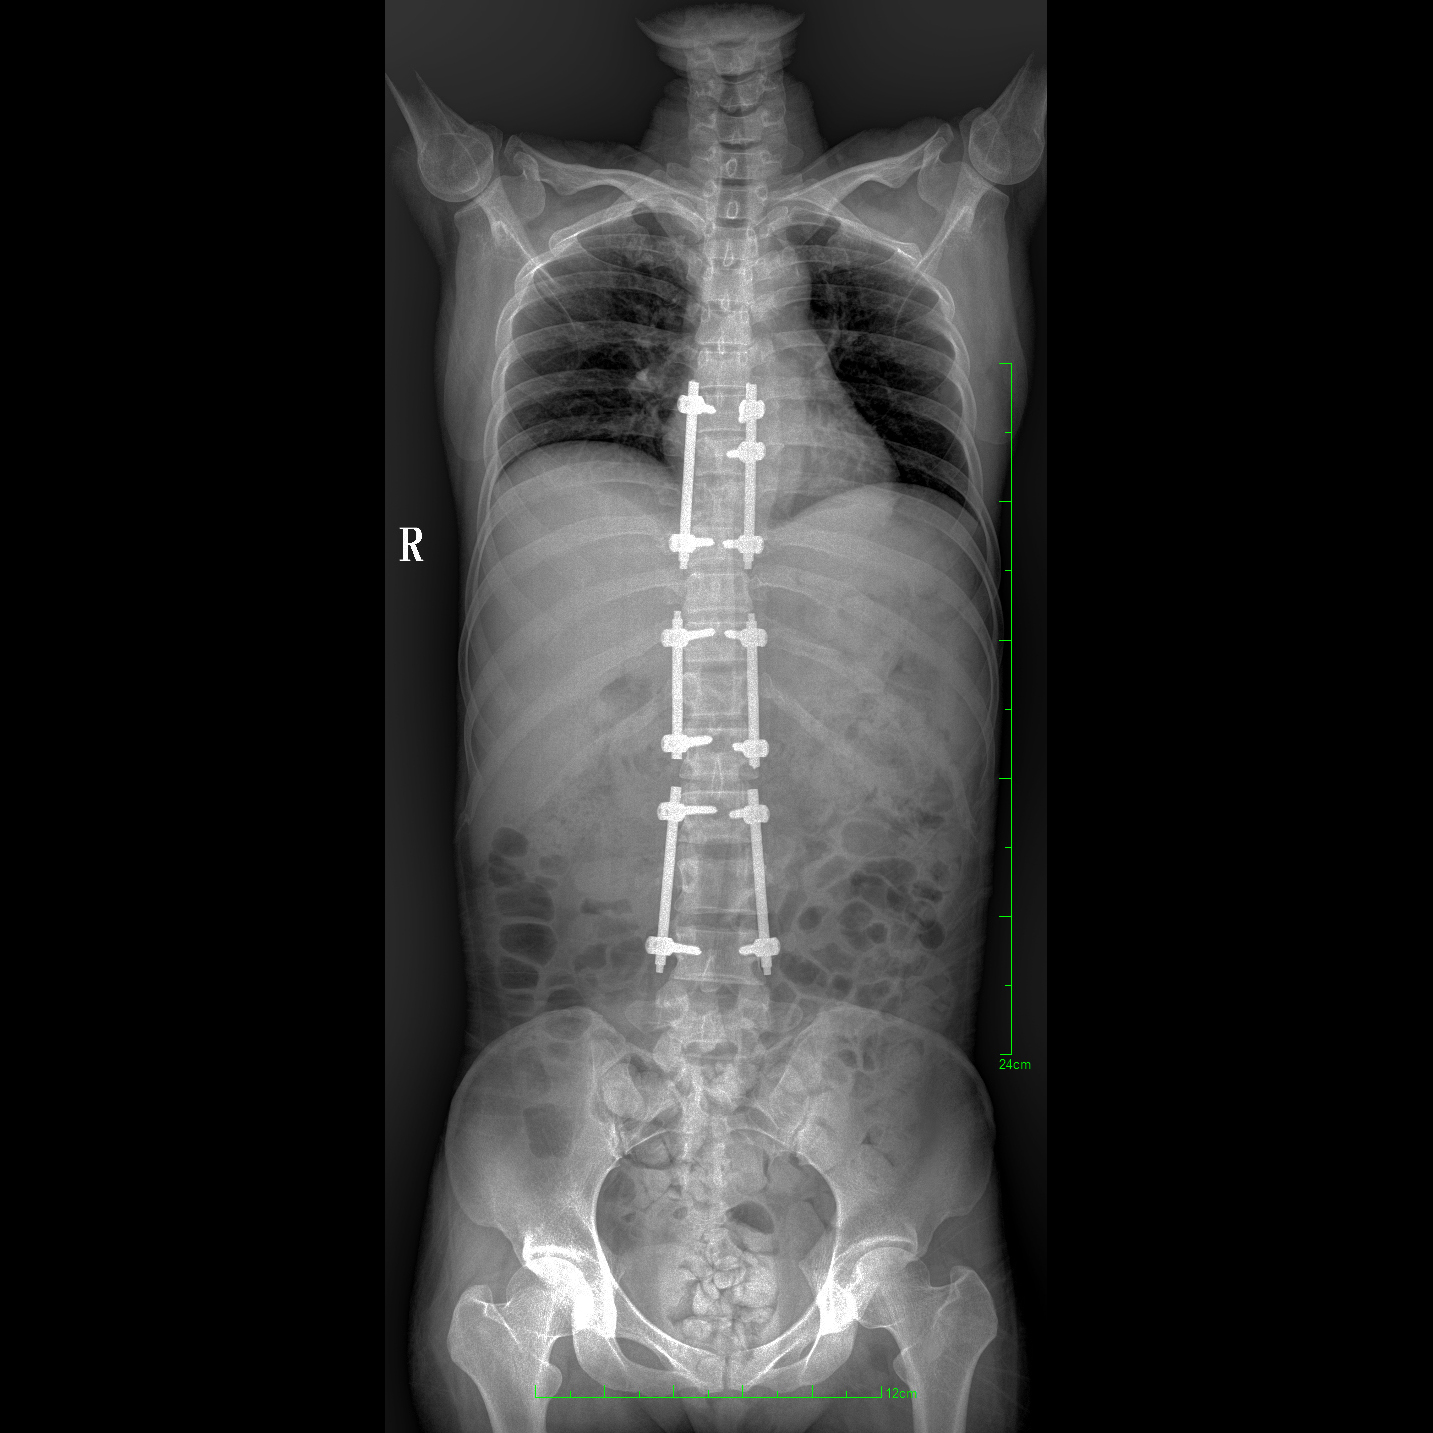

支持全脊柱攝影、雙下肢攝影、脊髓造影、復(fù)雜創(chuàng)傷、人工關(guān)節(jié)置換、關(guān)節(jié)損傷的修復(fù)重建等大視野臨床應(yīng)用

全脊柱一次成像 不拼接

17"*34"有效視野,一次成像不拼接。相較于多張攝影再軟件拼接的DR設(shè)備,PLX8600解決了拼接圖像存在密度不均勻,拼接處圖像配準(zhǔn)和放大效應(yīng)等問題,給臨床帶來了大視野影像解決方案,可一次性覆蓋全脊柱或雙下肢影像。

Clinical picture

臨床圖片